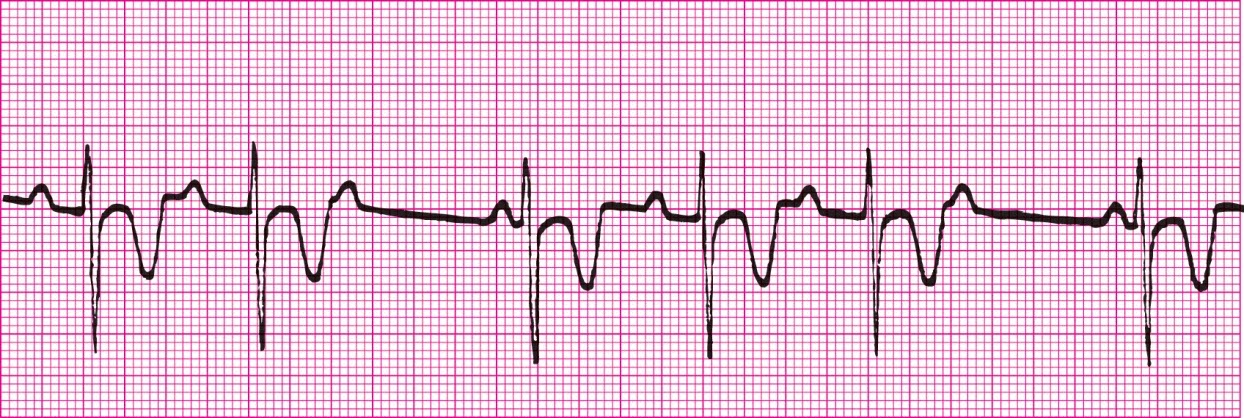

Second Degree Heart Block Type 1 (PRI gets longer each beat until beat is dropped)